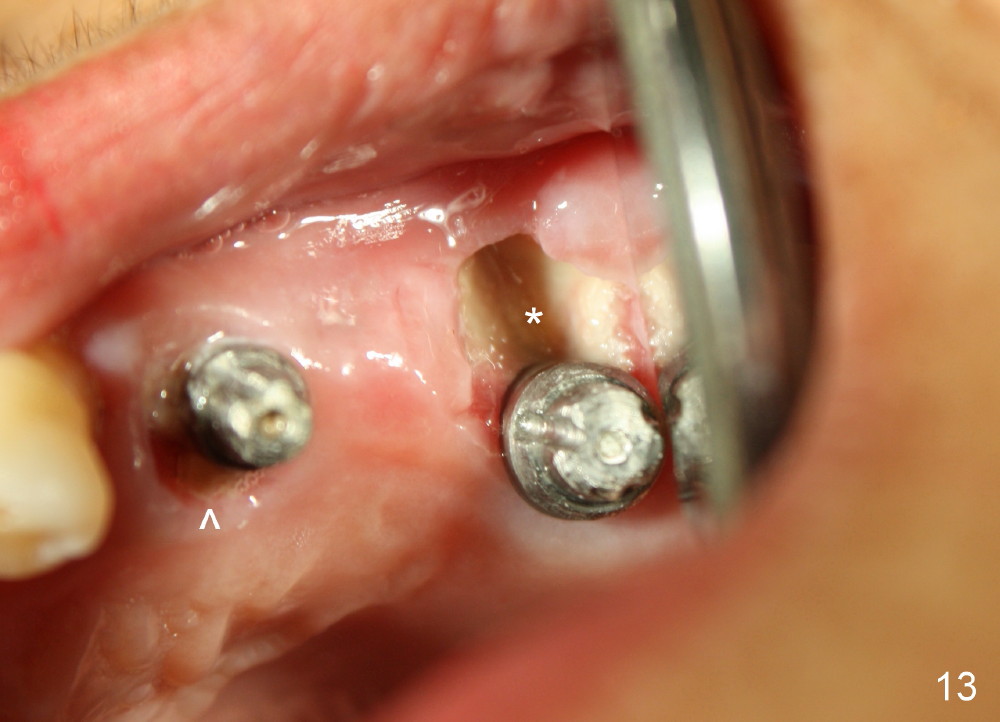

Buccal to #14 implant/abutment is a large defect, which is filled with allograft and Osteogen and covered by collagen membrane (Fig.9 M). The defect at the site of #12 is mesiopalatal, which is repaired in the same fashion (Fig.10: M). The collagen membrane is in turn protected by the "overhang" (extension) of the immediate provisional bridge (Fig.11,12 *). Once the wounds heal (Fig.13, 9 days postop), the extension is trimmed (Fig.14).

Two PAs are taken 5 months postop (Fig.15,16). Patterns of bone graft (*) between these PAs are different, which suggests presence of the graft buccal to the implant at the site of #14. Another piece of evidence of the graft is that the buccal socket heals (Fig.17 B) without implant thread exposure (Fig.19). These two implants are ready for definitive restoration (Fig.18-20). Fig.21 shows the final restoration 5 months post cementation.